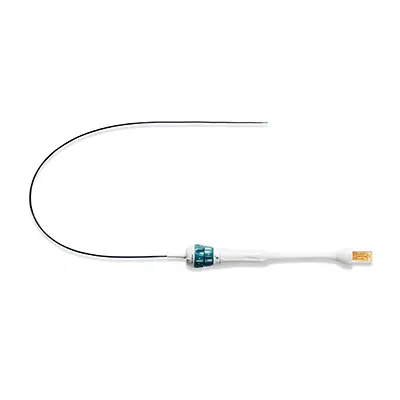

Чреспищеводные датчики используются в кардиологии для получения высококачественных изображений сердца в динамике в различных проекциях. Вводятся в грудную клетку пациента через пищевод. Датчик внешне и по управлению похож на гастрофиброскоп — имеет гибкую рабочую часть и гибкий дистальный кончик. Датчики различаются рабочей длиной, диаметром вводимой части и диаметром дистального кончика. Такие датчики требуют специальной дезинфекции и хранения, бережного обращения.

Датчики, совмещающие в себе видеогастрофиброскоп или видеобронхофиброскоп и ультразвук, называются EUS (Endoscopic Ultrasound) или эндоскопический ультразвук. По типу излучателя бывают конвексные, микроковексные и радиальные (с 360-градусным обзором). Являются примером мультимодального получения изображения, когда на одном экране отображается изображение с двух разнородных систем визуализации — с ультразвука и видео с эндоскопа.